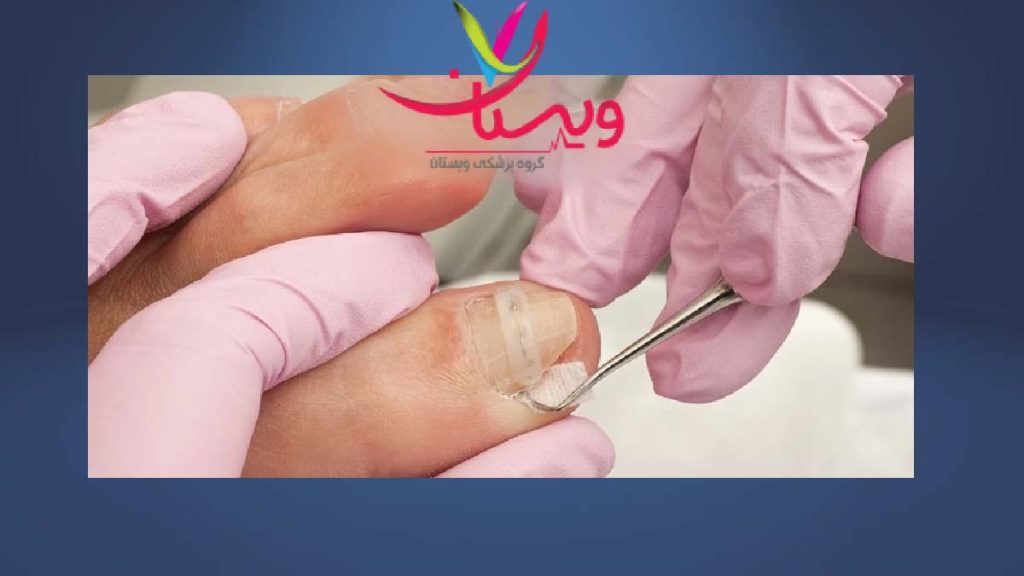

ناهنجاریهای ناخن و ایجاد فیبروما در اطراف آنها

4. جراحی ضایعات ناخنی و پوستی

✅ ضایعات فیبروما در اطراف ناخن یا ضایعات ضخیم پوست (مانند شگرین پچ):

- اگر دردناک باشند یا در فعالیتهای روزمره اختلال ایجاد کنند، جراحی سرپایی برای برداشتن آنها انجام میشود.

- این جراحیها ساده و کمخطر هستند و بیشتر با هدف زیبایی یا راحتی انجام میگیرند.

- ضایعات ناخنی (Periungual Fibromas):

- تومورهای کوچکی هستند که در اطراف یا زیر ناخنها شکل میگیرند.

- ممکن است دردناک باشند و روی عملکرد انگشتان تأثیر بگذارند.